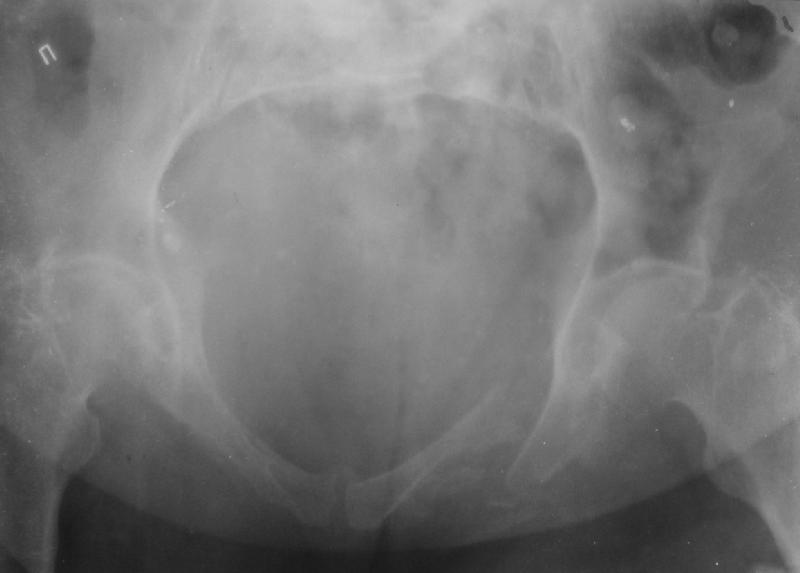

Здравствуйте уважаемые коллеги! Поступила пациентка, 61г, через 1 месяц после травмы, с двусторонним ротационно-нестабильным повреждением тазового кольца: перелом боковых масс крестца с обеих сторон, переломы лонной и седалищной костей слева, отрывные переломы передних остей левой подвздошной кости, сегментарный перелом левой подвздошной кости. Кроме того у пациентки имеется сегментарный перелом левого бедра. Перелом бедра не вызывает вопросов - планируем блокируемый остеосинтез стержнем, а вот при обсуждении тактики лечения переломов костей таза возник вопрос о необходимости синтеза остей подвздошной кости, учитывая сроки с момента травмы и наличие остеопороза могут возникнуть технические сложности. Если у кого-нибудь собственный опыт или ссылки на литературу об отдаленных результатах при не восстановлении сгибательного аппарата бедра?

Уважаемые коллеги, в продолжение обсуждения перелома костей таза с отрывами остей досылаю R-снимки (КТ и КТ с 3d реконструкцией)